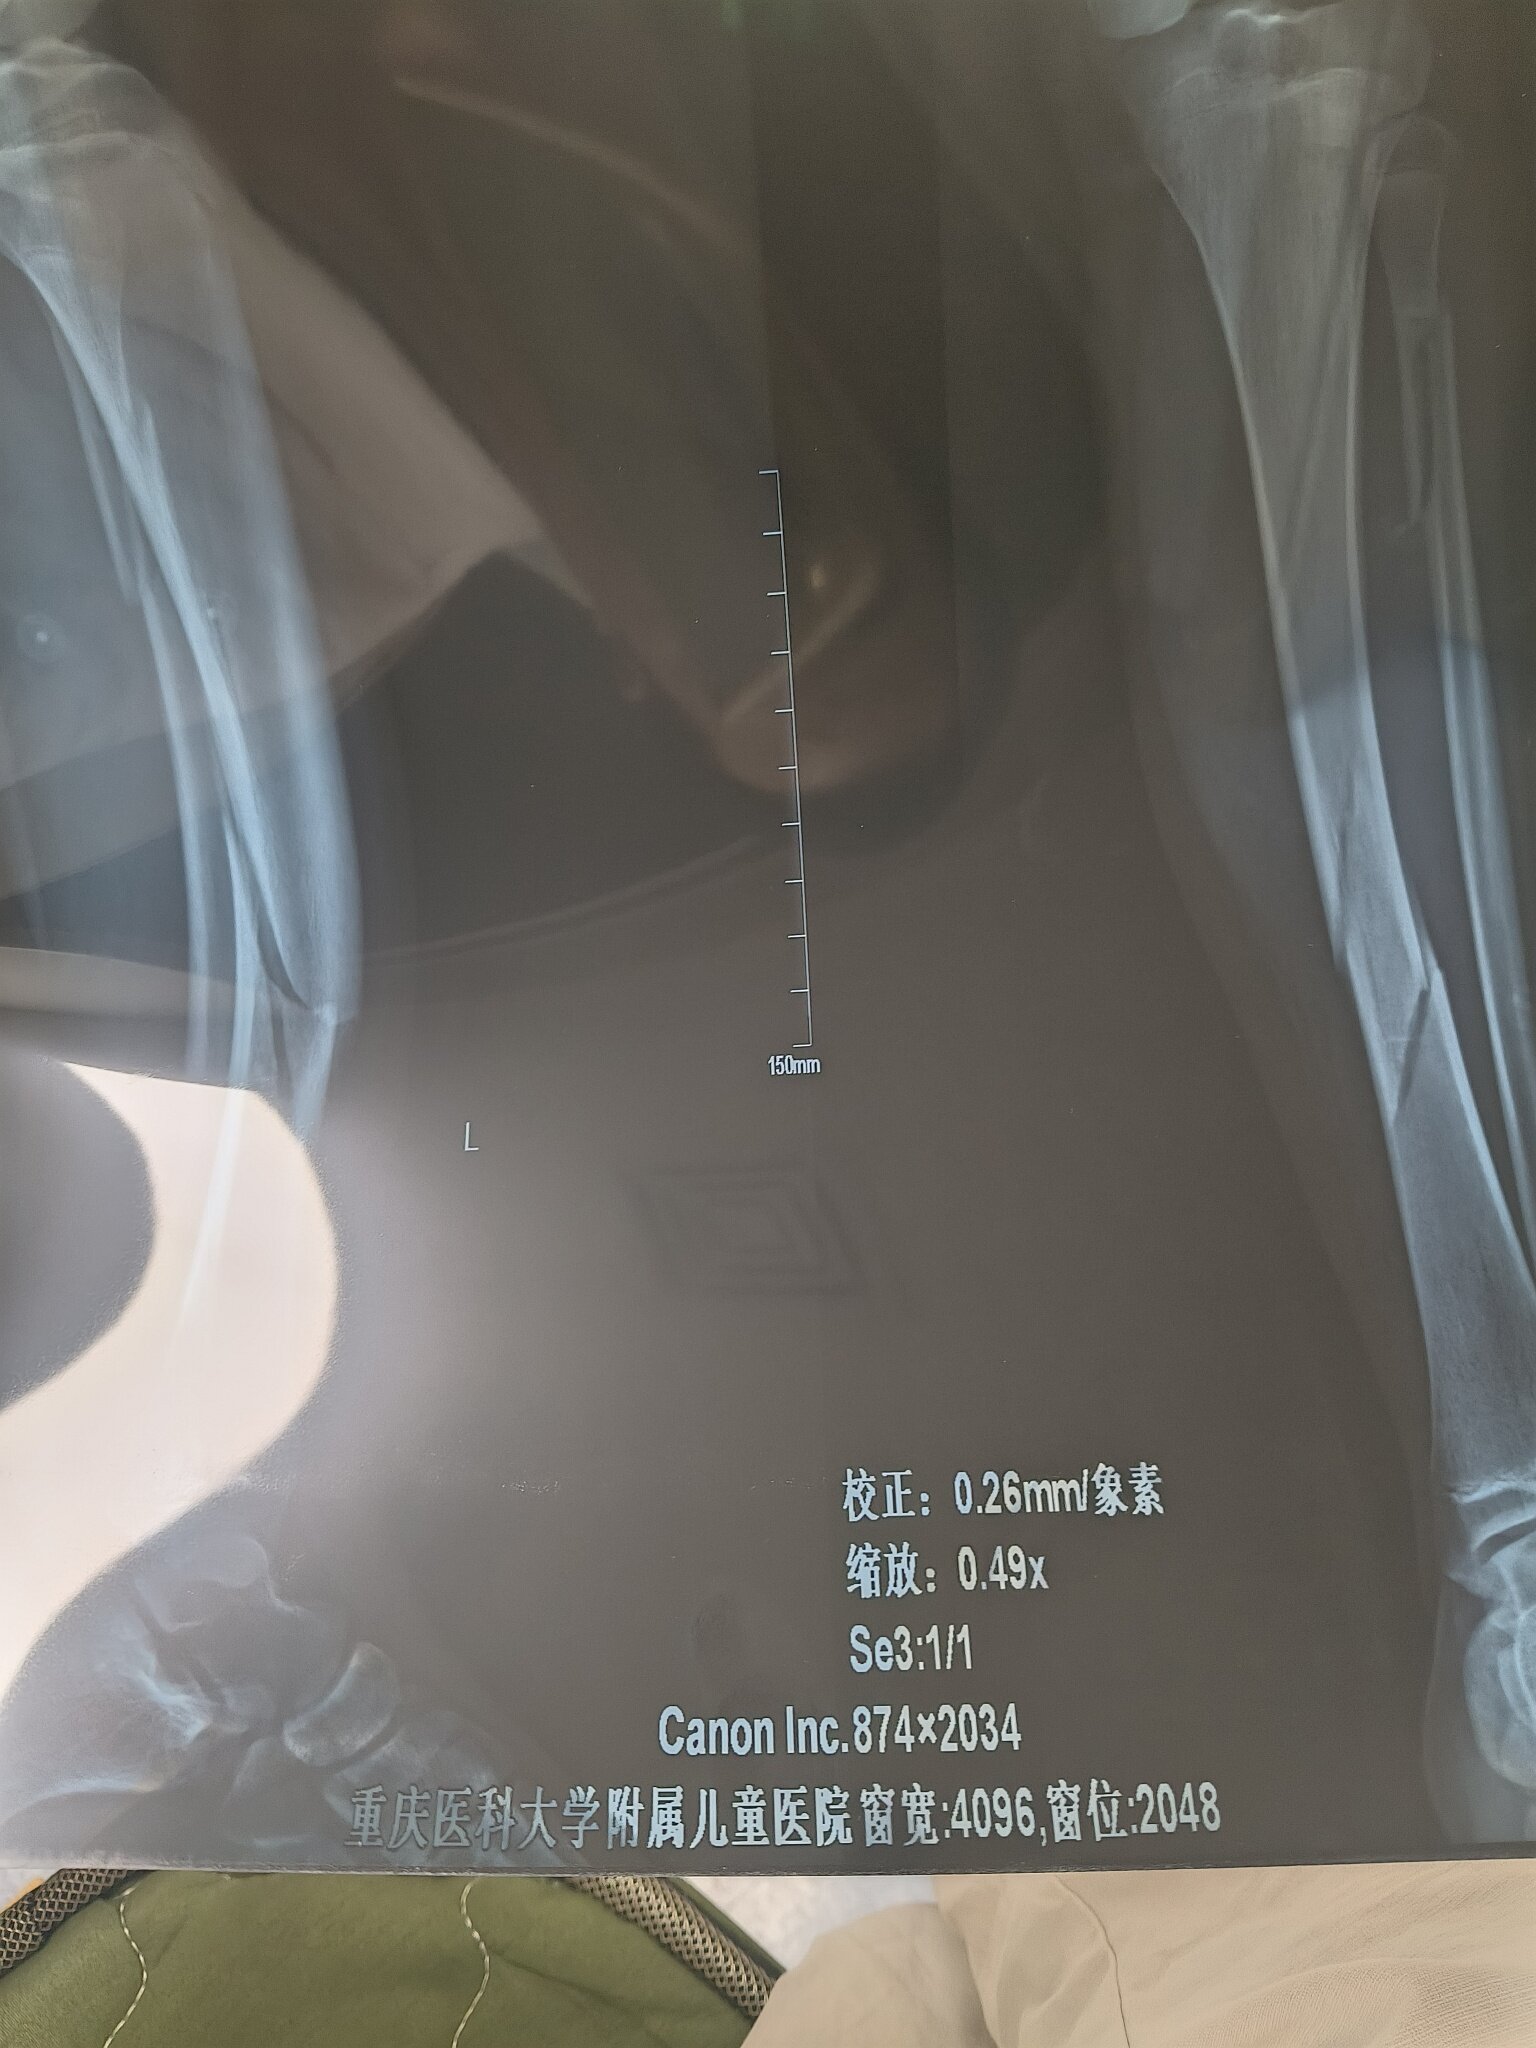

多少岁?从片子上看,只是骨折,没多大移位,可以直接固定山与城 发表于 2025-07-02 16:58